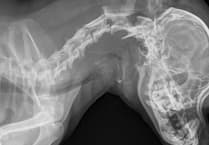

- Limb fractures